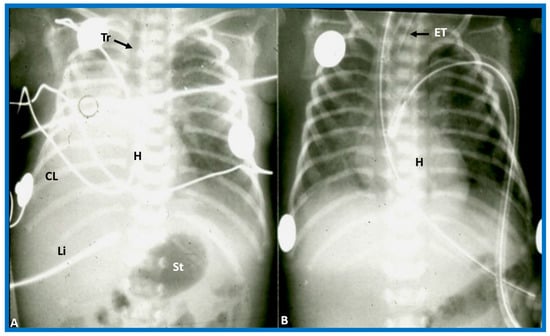

Figure 2. Chest X-rays of two different newborn babies with hearts situated in the right chest, i.e., dextrocardia. (A) The liver (Li) is visualized across the abdominal cavity without seeing the stomach air bubble; thus, it is not possible to establish the visceral situs. (B) On the other hand, the stomach (St) air shadow is faintly seen on the right side of the abdomen while the Li is imaged on the left side. The findings in (B) indicate inversion of the visceral position, situs inversus. Furthermore, the location of the St on the right is established by the location of the NG (nasogastric) tube. Air in the intestine is seen in the lower portion of the abdomen in both infants. ET, endotracheal tube. Reproduced from reference [4].

Figure 3. Chest X-ray of a child demonstrating the heart in the right chest (dextrocardia). The positions of the liver (Liv) on the right side, and stomach (Sto) on the left side are seen, indicative of visceral situs solitus. This is described as isolated dextrocardia. Tr. Trachea; inverted L, indicates left. Sternal and pacemaker wires (not labeled) are seen and are related to prior surgery. Modified from reference [5].

Figure 15. (A) Chest X-ray of a baby who had collapsed right lung (CL), pulling the heart (H) to the right, causing dextroposition of the H. The trachea (Tr) is shifted to the right side. The liver (Li) and stomach (St) bubble are in the normal position (situs solitus). (B) Following endotracheal (ET) intubation and suctioning, the right lung expanded, returning the H to its normal position. Modified from reference [4].